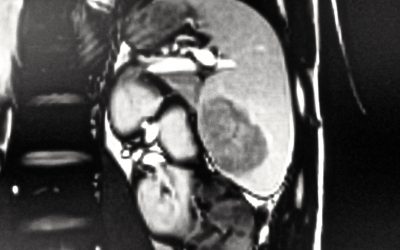

Neoformazione solida solitaria primitiva della milza: percorso diagnostico-terapeutico

di Enrico Ganz Nell’uso clinico, per “neoformazione solida primitiva della milza” si intende una malformazione o un tumore, benigno o maligno, che origina dal tessuto splenico, distinguendosi perciò dalle metastasi, che occasionalmente colonizzano la milza. Il...